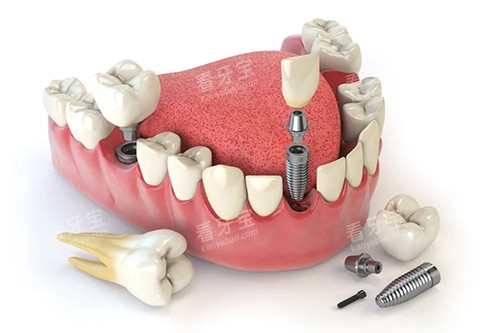

3000 + 成功种植实例

沈阳国民口腔门诊部在种植牙领域取得了显著的成绩,积累了 3000 + 成功种植实例。

这些成功的种植病例不仅证明了门诊部医生的正规技术水平,也让更多的患者对门诊部的种植牙技术充满信心。

许多患者在接受种植牙治疗后,修养了良好的咀嚼功能和美观的牙齿外观,对治疗结果非常满意。